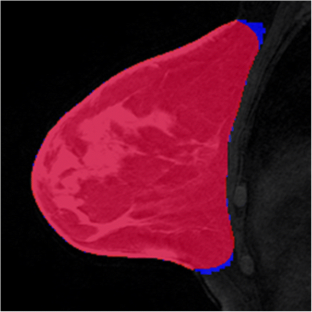

Fig. 5